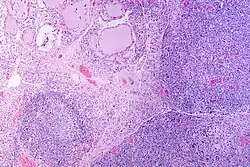

| A micrograph of the thyroid of someone with Hashimoto's thyroiditis | |

Gross morphological changes within the thyroid are seen in the general enlargement, which is far more locally nodular and irregular than more diffuse patterns (such as that of hyperthyroidism). While the capsule is intact and the gland itself is still distinct from surrounding tissue, microscopic examination can provide a more revealing indication of the level of damage.[55] Hypothyroidism is caused by replacement of follicular cells with parenchymatous tissue.[52]

Pathology

Gross pathology of a thyroid with autoimmune thyroiditis may show a symmetrically enlarged thyroid.[5] It is often paler in color, in comparison to normal thyroid tissue, which is reddish-brown.[5]

Microscopic examination (histology) will show lymphocytes (including plasma B-cells) diffusely infiltrating the parenchyma.[55] The lymphocytes are predominately T-lymphocytes with a representation of both CD4+ and CD8+ cells.[5] The plasma cells are polyclonal, with present germinal centers resembling the structure of a lymph node[5] (also called secondary lymphoid follicles, not to be confused with the normally present colloid-filled follicles that constitute the thyroid).[55]

In late stages of the disease, the thyroid may be atrophic.[10] Colloid-filled follicles shrink, and the cuboidal cells that usually line the follicles become Hürthle cells.[5] Fibrous tissue may be found throughout the affected thyroid as well.[5] Severe thyroid atrophy presents often with denser fibrotic bands of collagen that remain within the confines of the thyroid capsule.[55]

Generally, pathological findings of the thyroid are related to the amount of remaining thyroid function — the more infiltration and fibrosis, the less likely a patient will have normal thyroid function.[5] A rare but serious complication is thyroid lymphoma, generally the B-cell type, non-Hodgkin lymphoma.[24]